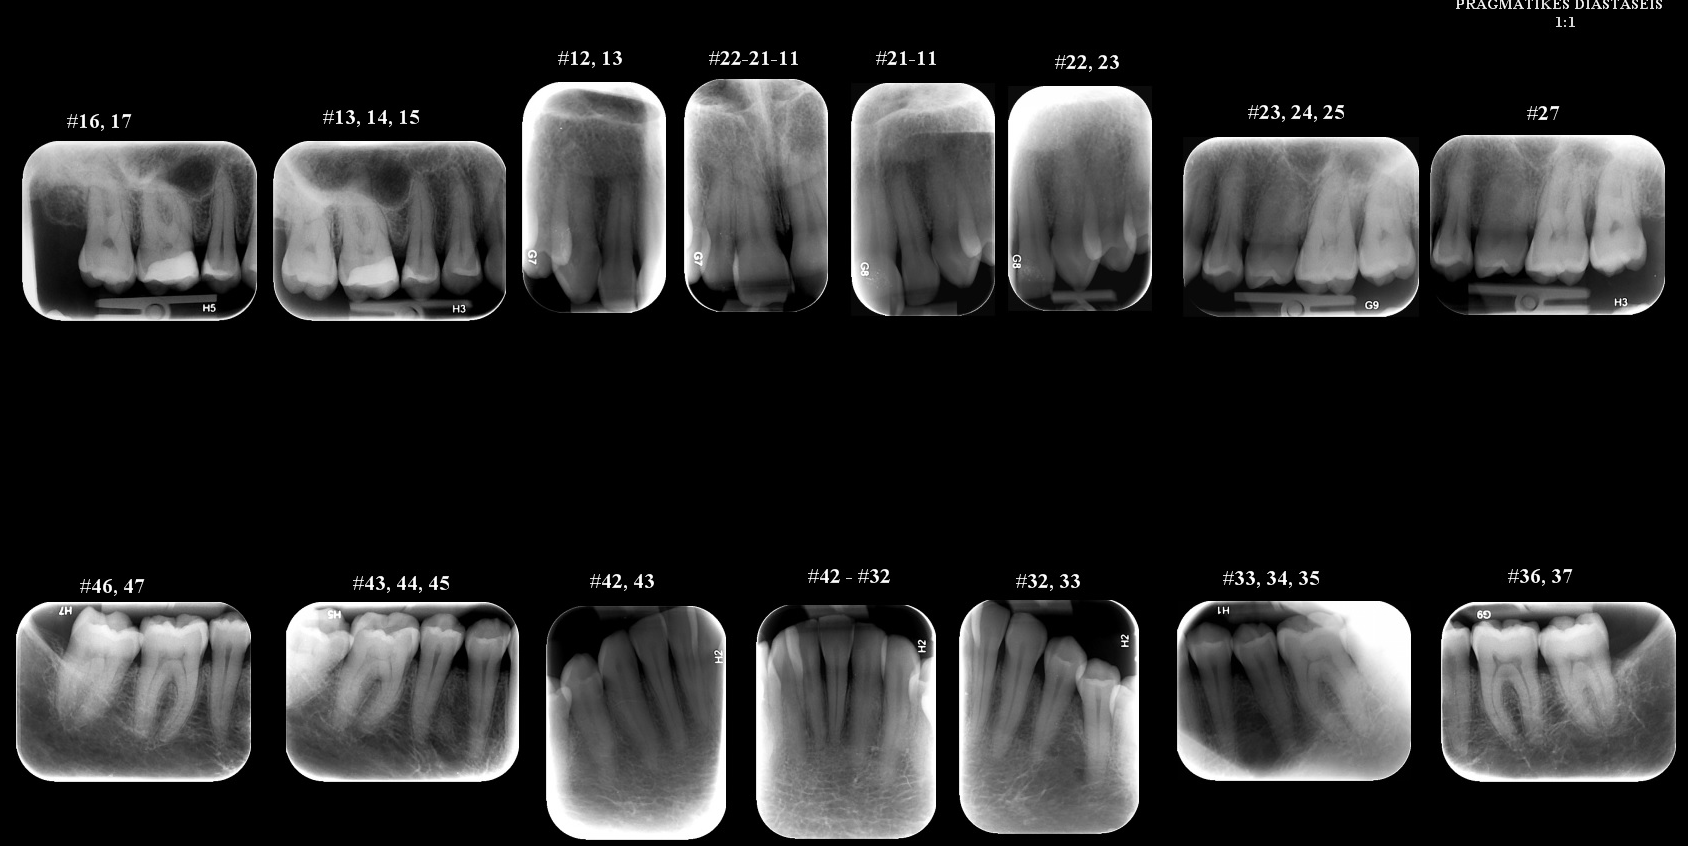

2. FULL-MOUTH ΟΠΙΣΘΟΦΑΤΝΙΑΚΕΣ  ΑΚΤΙΝΟΓΡΑΦΙΕΣ

Πρόκειται για ένα σετ 14-16 οπισθοφατνιακών ακτινογραφιών, οι οποίες λαμβάνονται διαδοχικά προκειμένου να απεικονιστούν όλα τα δόντια της άνω και κάτω γνάθου.